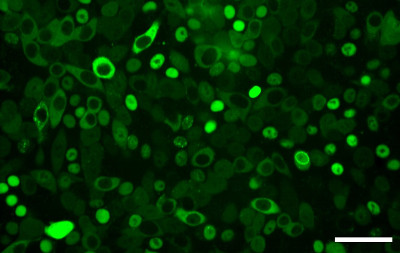

“While a traditional small-molecule drug binds to a protein of interest and inhibits some sort of biochemical function of that protein, we developed a therapeutic modality that would recruit the protein to an E3 ligase to activate the ubiquitin-protease system,” explains Winter. “When we recruit the protein of interest in the vicinity or proximity of such an E3 ligase, we can trick the ligase into putting the ubiquitin moieties on the protein of interest, earmarking it for degradation by the proteosome.” The technique enables robust, selective and fast elimination of proteins in cellular assays and in vivo and also offers better outcomes in regard to dosing, side effects and drug resistance.